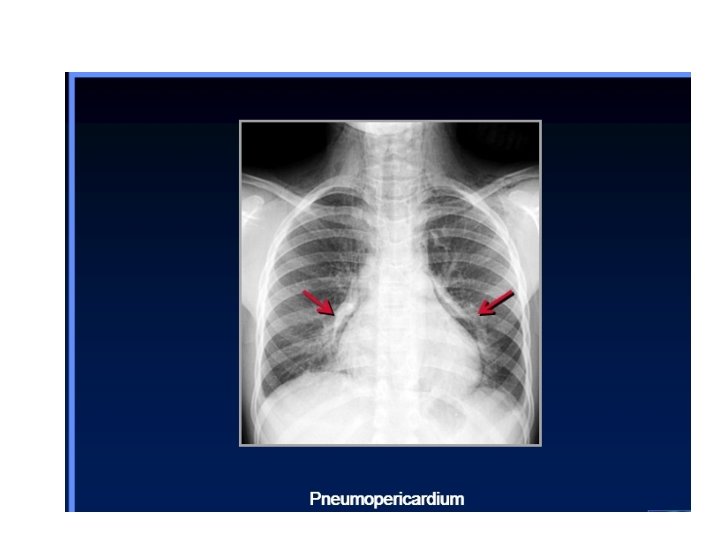

Continuous diaphragm sign